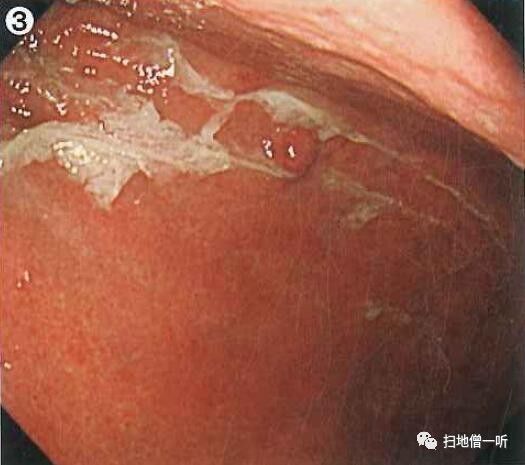

边缘观察可见粘膜粗大,需考虑增生性息肉?顶部可见轻微凹陷,粘膜结构消失

NBI下观察其病变边缘粘膜粗大,顶部凹陷,粘膜结构消失,期间可见粗大蛇形血管

靛胭脂染色后观察仍可见病变边缘粘膜粗大,顶部凹陷结构消失,呈黄色点,伴扩张血管。边缘部黄圈内粘膜粗大呈非肿瘤性增生性粘膜表现,但是顶部无粘膜结构区与增生性息肉相矛盾,中心凹陷伴SMT样隆起,黄色调伴血管扩张考虑是否存在神经内分泌肿瘤可能